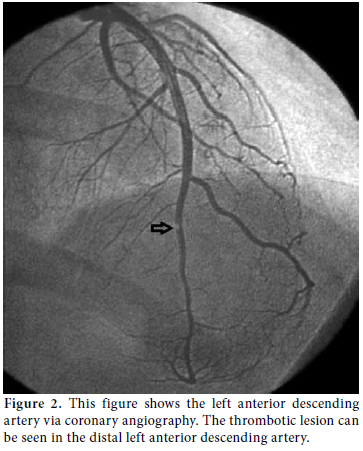

Consultations were then held with the pulmonary medicine and rheumatology departments regarding the eosinophilia identified in the CBC, pulmonary opacities revealed via chest X-ray, and the patient's past history of asthma (Figure 3). Furthermore, cranial computed tomography (CT) was performed on the day after the angiography which showed neurological involvement or paranasal sinus abnormality with a prediagnosis of CSS. The results of the cranial CT were also consistent with chronic sinusitis. The presence of asthma, hypereosinophilia of >10%, chronic sinusitis, and pulmonary opacities represent four of the six ACR criteria required for the diagnosis of CCS.[5] Our patient tested negative for anti-nuclear antibodies (ANAs), anti-double stranded DNA (antidsDNA), extractable nuclear antigens (ENAs) and anti-neutrophil cytoplasmic antibodies (ANCAs). The corticosteroid methylprednisolone at an initial dosage of 80 mg per day (1 mg/kg/d) was prescribed after the termination of the tirofiban infusion. Afterwards, the patient's eosinophil levels in the CBC decreased to normal ranges, and symptomatic relief was completely provided. Control coronary angiography was performed one week later, and the thrombotic lesions had disappeared (Figure 4). In addition, chest radiographs showed complete resolution of the opacities (Figure 5). After two more weeks, control echocardiography was performed revealing a normal morphology of the ventricles without any segmental wall motion abnormalities. Furthermore, the pericardial fluid had also disappeared.